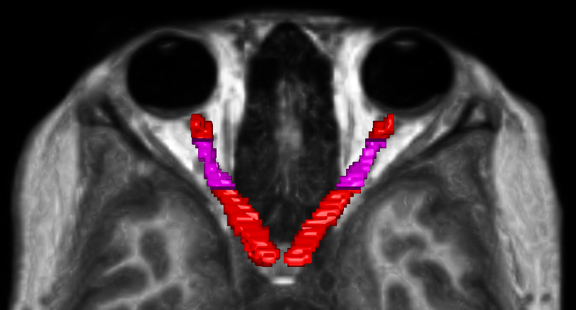

Step 4 and 5 are necessary because the initial registration introduced an offset in the segmentations. Therefore, the ROI co-registration step corrects this misalignement, as illustrated in the example below: red represents the MP2RAGE segmentation, green represents the DWI segmentation after the initial alignment, and blue represents the DWI after the ROI alignment correction.

Additionally, outlying values were identified near the edges of both manual segmentations. To ensure plausible values along the optic nerve, Regions of Interest (ROIs) were defined, as illustrated in the example figure below.